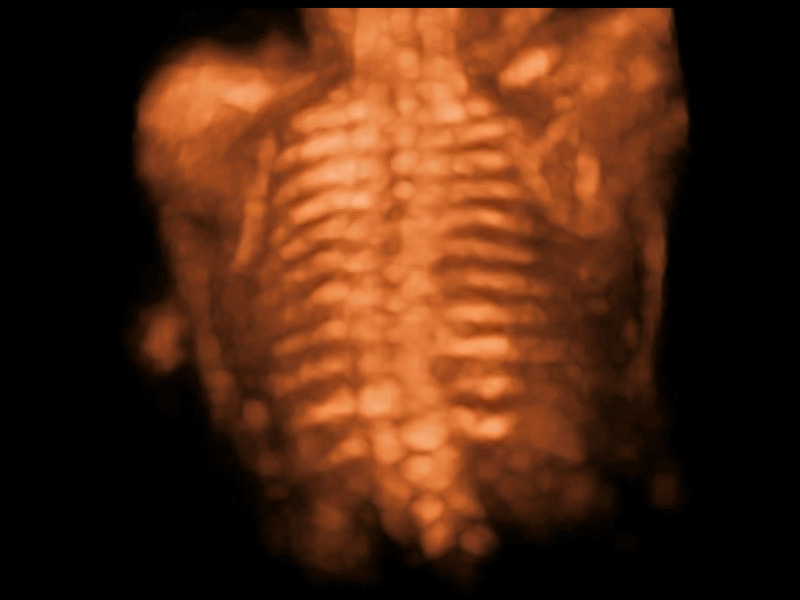

S-Fetus基于大数据深度学习算法,能够帮助您在产前筛查过程中智能识别胎儿标准切面、自动测量并录入报告。一个按键,即可智能、精准、高效地获取胎儿生理指标,极大简化您的产科检查操作。

可快速对产科扫查切面完成胎儿生理学参数的自动测量,减少操作者按键次数,大幅提升检查效率。